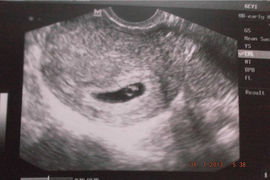

на 6 неделе беременности

Что есть на 6 неделе беременности 84 фото